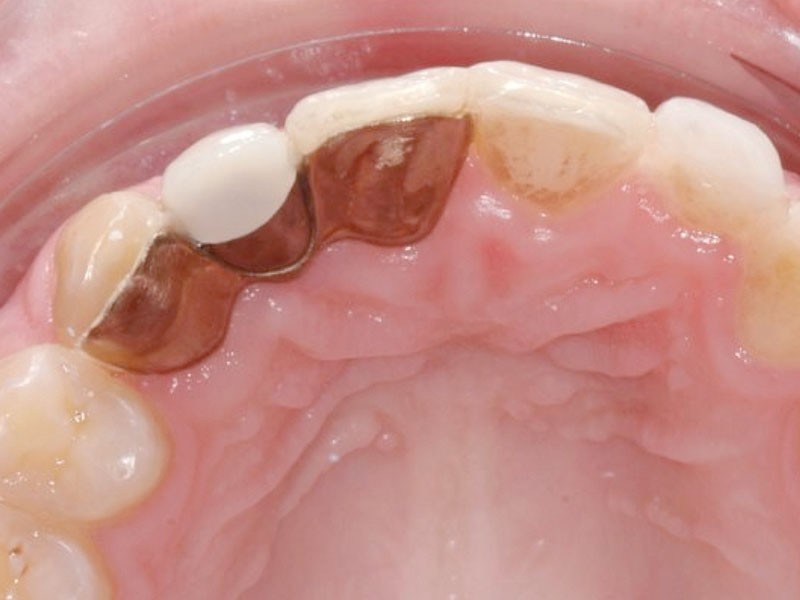

Différentes solutions thérapeutiques ont été utilisées au cours du temps pour compenser les édentements consécutifs aux agénésies d’incisives latérales. Les deux plus récentes sont les bridges collés et les implants. Les bridges collés ont fait leur apparition dans les années 1970. Plus élégante que le bridge conventionnel, cette option diminuait considérablement la mutilation des dents bordant l’édentement, une préparation minimale des faces linguales étant nécessaire. Malgré tout, dans les faits, la réalisation de ces bridges collés semble encore aujourd’hui, réservée à des experts de la prothèse conjointe (fig. 1).